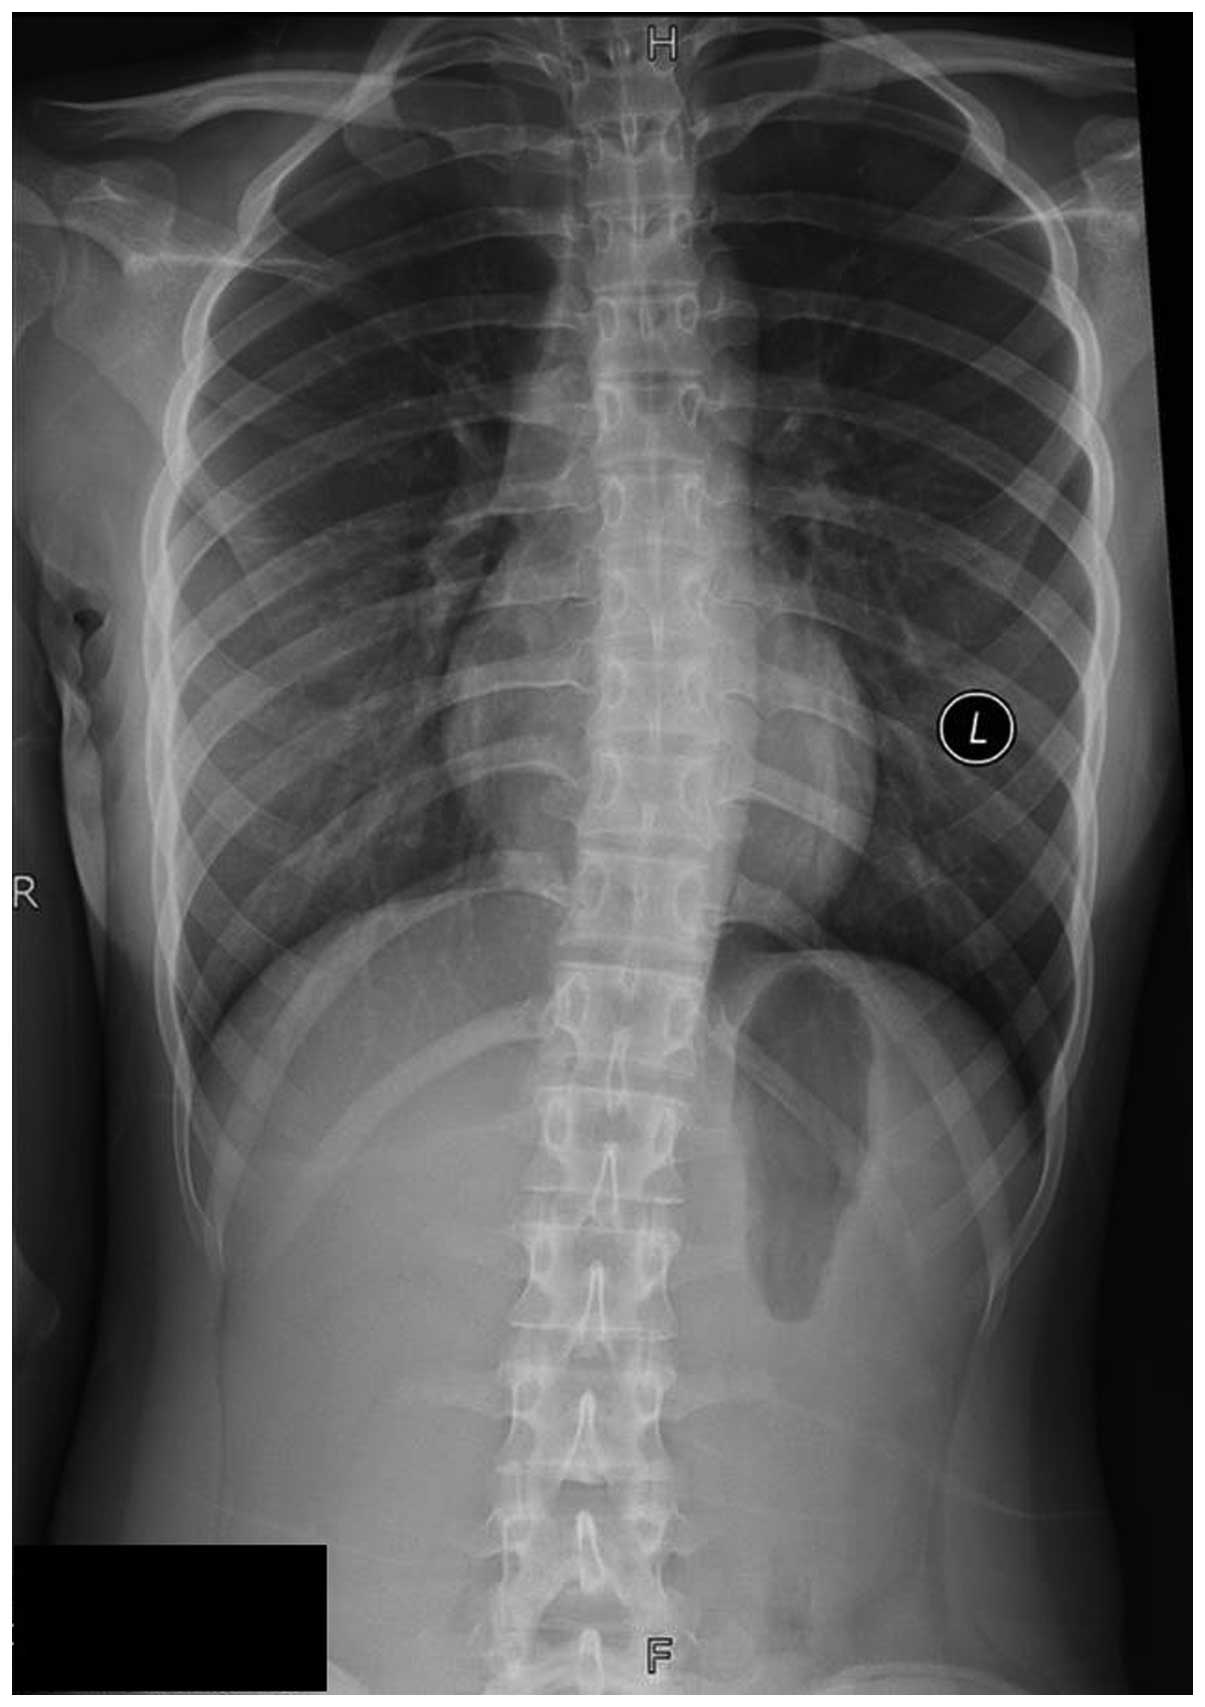

Остеома ребра: примеры рентгенограмм и диагностические признаки